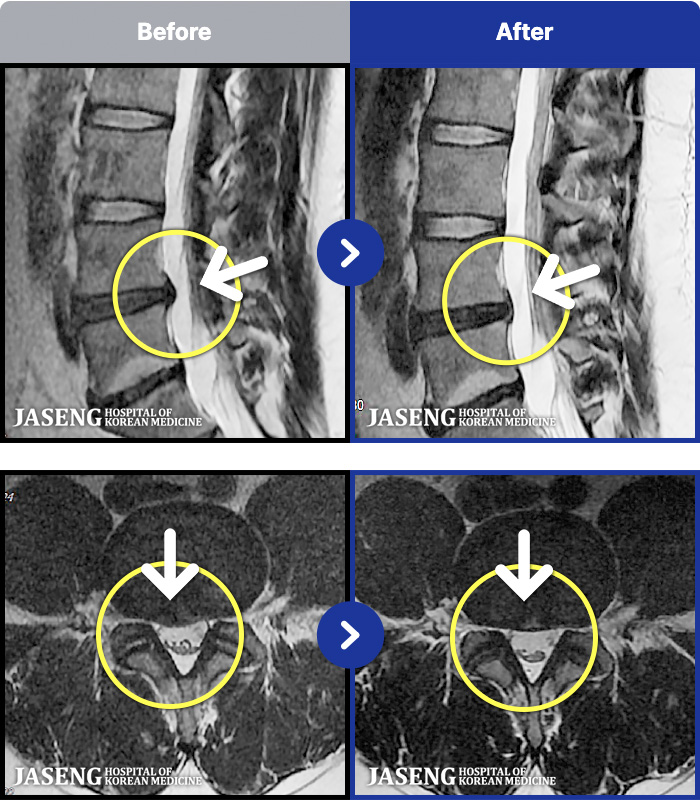

MRI ġ

MRI ũ ʸ Ȯϼ.